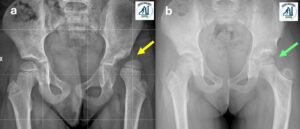

Displasia evolutiva dell’anca

Utilizziamo Tecniche chirugiche moderne e di eccellenza per intervenire sulla patologia “Displasia evolutiva dell’anca“